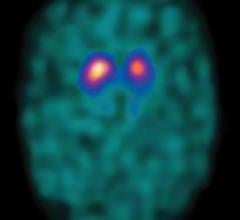

July 19, 2011 – The study "Use of Florbetapir-PET for Imaging beta-amyloid Pathology," published in the Jan. 19, 2011 ...

July 5, 2011 – The first radiopharmaceutical imaging agent to help physicians evaluate patients with suspected ...